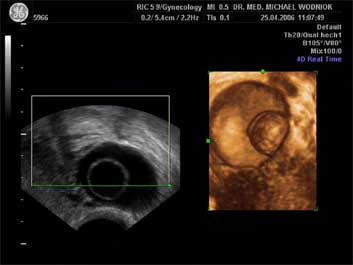

Ultraschall des kleinen Beckens mit der Vaginalsonde Die Ultraschalluntersuchung ist ein bildgebendes Verfahren, welches die Reflektion oder Echos von Ultraschallwellen in den unterschiedlichen Geweben und Organen ausnützt um computergestützt Schnittbilder aus dem Inneren des Körpers zu erstellen. Durch moderne hochleistungsfähige Mikroprozessoren ist es in den letzten Jahren möglich geworden, auch 3-dimensionale oder sogar bewegte 3-dimensionale (4-D) Bilder bzw. Bildsequenzen zu erzeugen. Beides können wir Ihnen in der Praxis anbieten. Eine Ultraschalluntersuchung ist ungefährlich und schmerzfrei. Durch die Anwendung von Dopplerverfahren, mit welchen wir den Blutfluss in den Organen feststellen und messen können, erweitern wir die Untersuchung um die funktionelle Dimension. Ein weiterer Bestandteil unseres Leistungsspektrums ist die farbkodierte Dopplersonographie. Farbkodiert sind entweder die Richtung des Blutflusses oder dessen Intensität. Über die computergestütze Berechnung des Blutflusswiderstandes ist im Einzelnen eine Aussage bzw. Vorhersage über die qualitative und quantitative Durchblutung möglich. (Plazentadurchblutung, kindliche Blutgefässe, Durchblutungsmuster bei verschiedenen Tumoren des Unterleibes und der Brustdrüsen) Ultraschalluntersuchungen haben in unserem Fachgebiet vielfältige Anwendungsmöglichkeiten gefunden. Besonders faszinierend ist der Einsatz im Bereich der vorgeburtlichen Diagnostik. Bereits in der 10. Schwangerschaftswoche ist es möglich, die Extremitäten des Embryos darzustellen und Aussagen zum Körperumrissbild zu machen (Ausschluss von Spaltbildungen, Nackentransparenzmessung). Auch im Bereich der Gynäkologie ist die Bedeutung des Ultraschalls stetig gewachsen und hat sich als erweiterte Vorsorge etabliert. Durch die vaginale Ultraschalluntersuchung können bereits kleine Veränderungen entdeckt werden, die sich der manuellen Tastuntersuchung noch entziehen. Auffällige Tastbefunde an den Eierstöcken sind durch den Einsatz von 3D / 4D in Kombination mit der Farbdoppleruntersuchung besser interpretierbar und können dadurch Frauen unnötige abklärende Operation ersparen. Die Anwendung des 3D Ultraschall, insbesondere im Coronarschnitt, lässt eine effektive Beurteilung für Veränderungen (Polypen, Karzinome) der Gebärmutterschleimhaut zu. ![]() ![]() ![]() ![]()